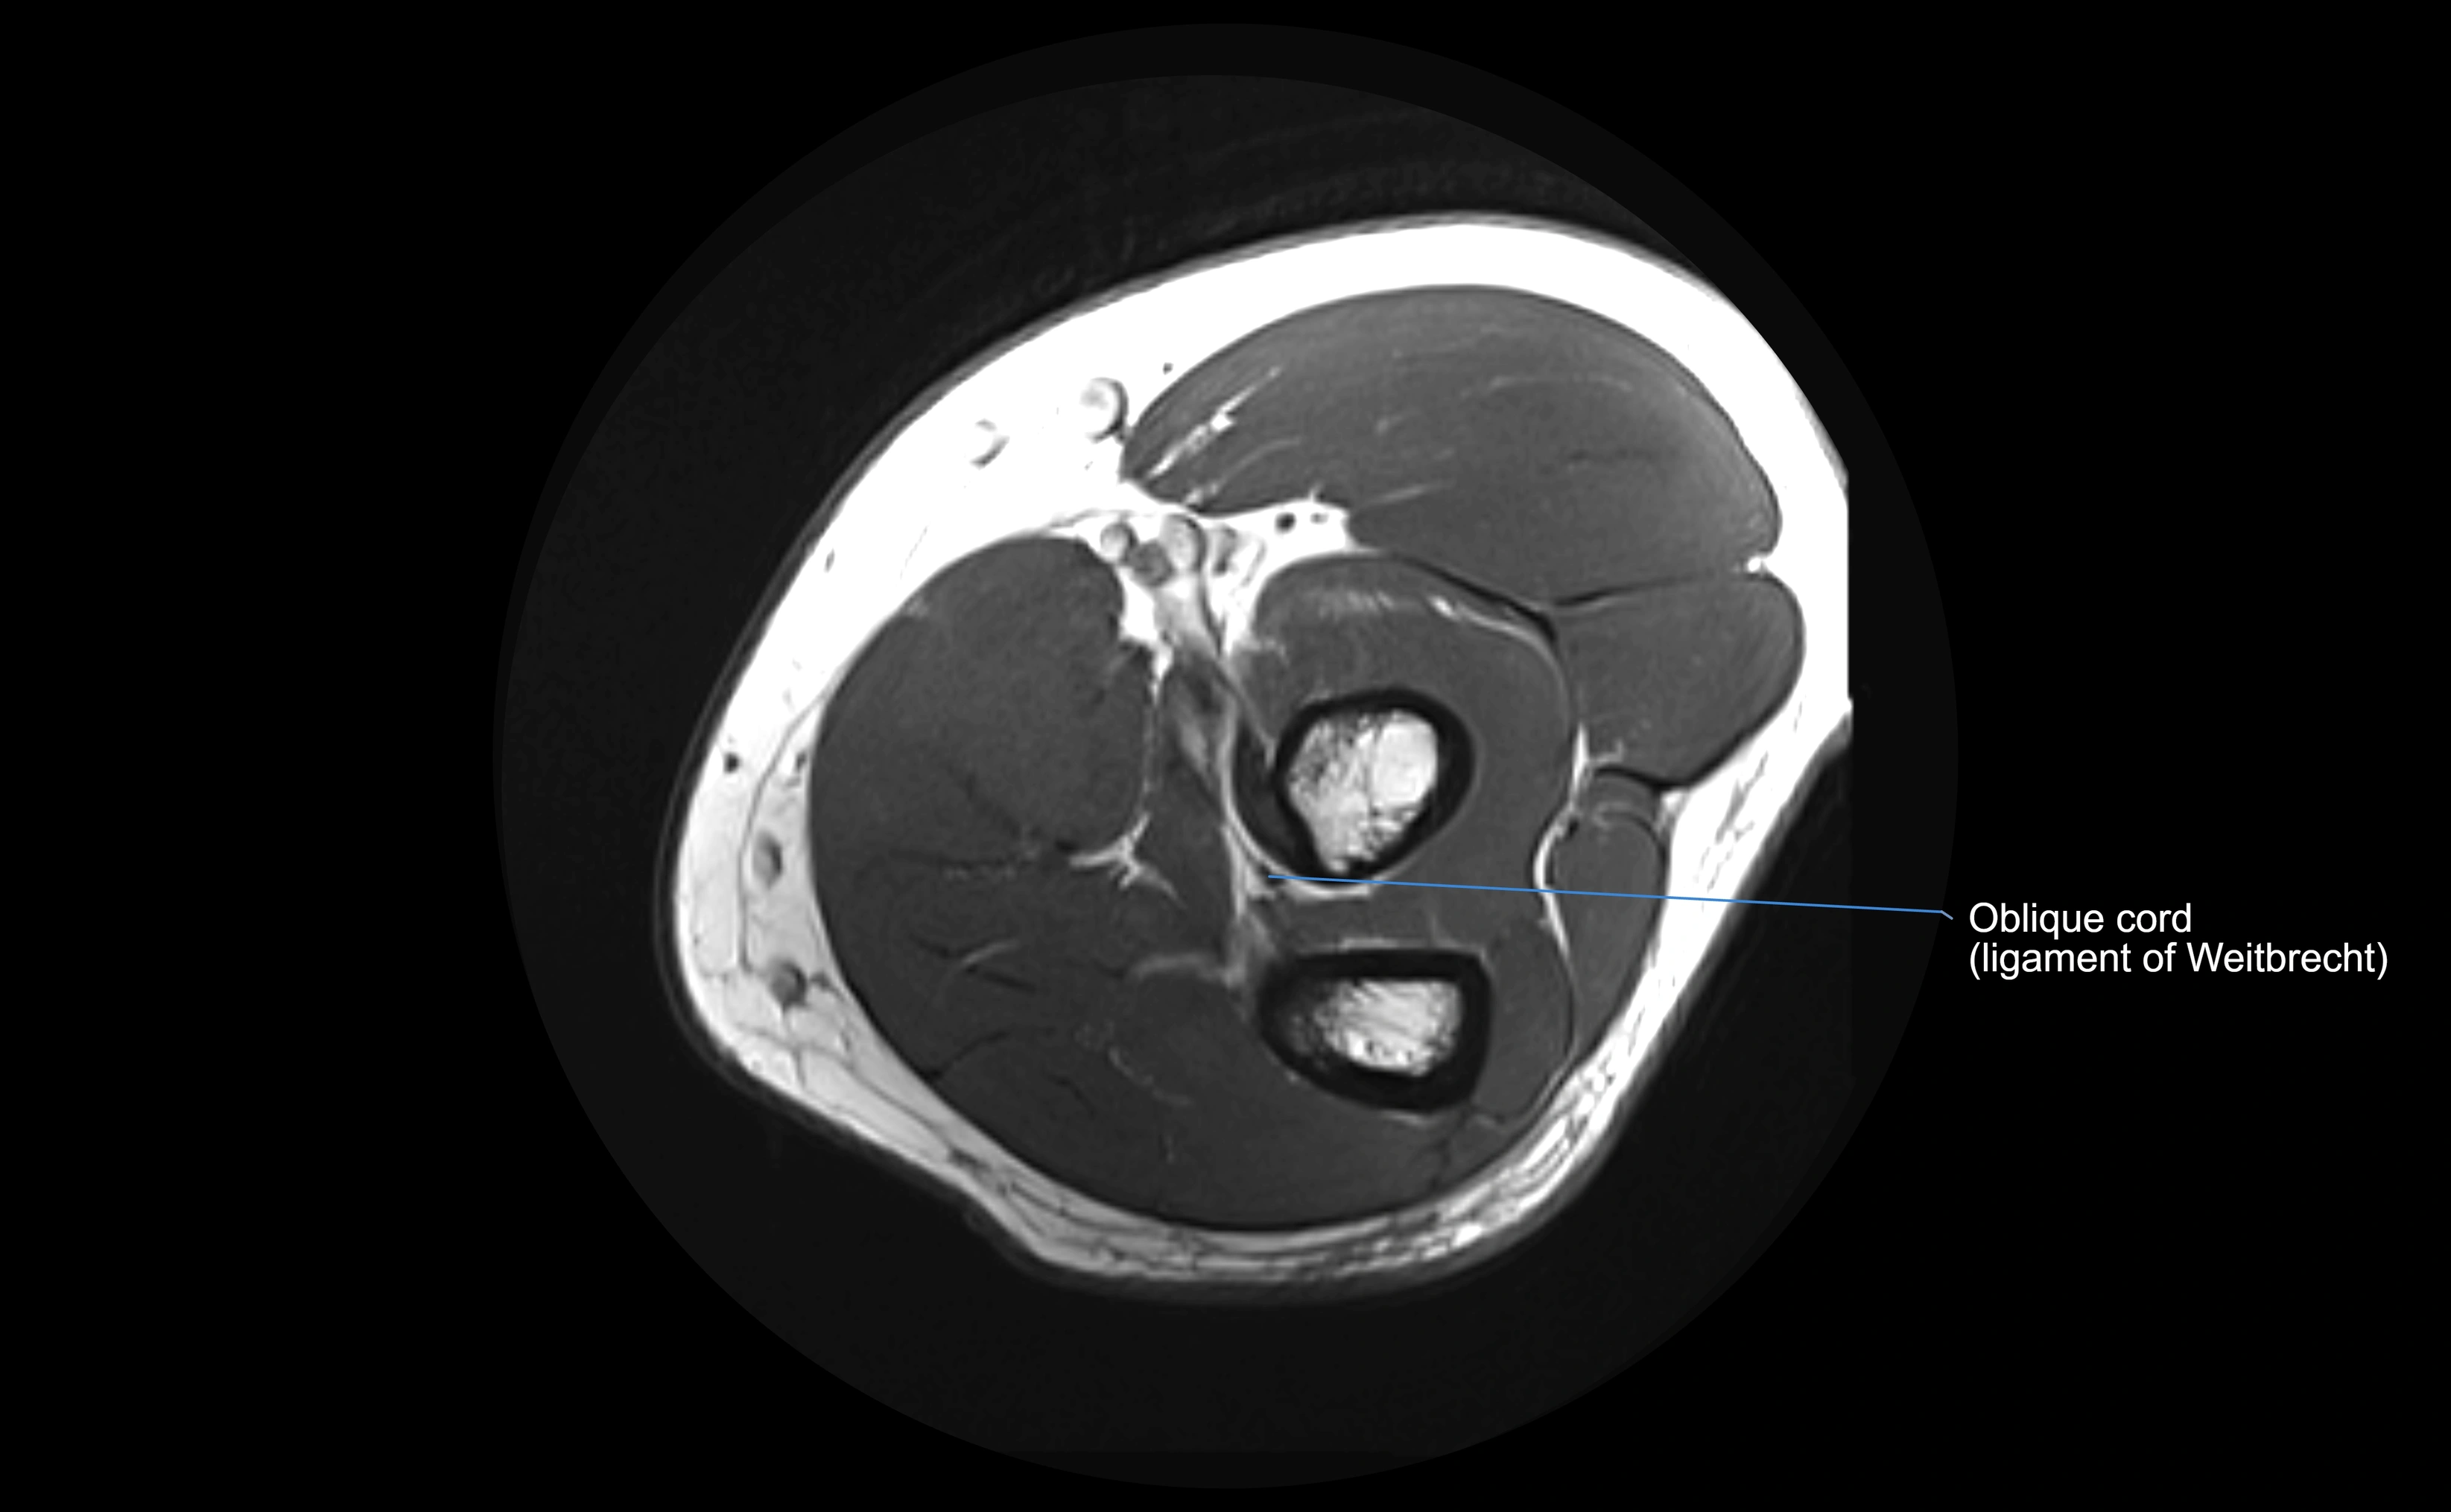

MRI images

image